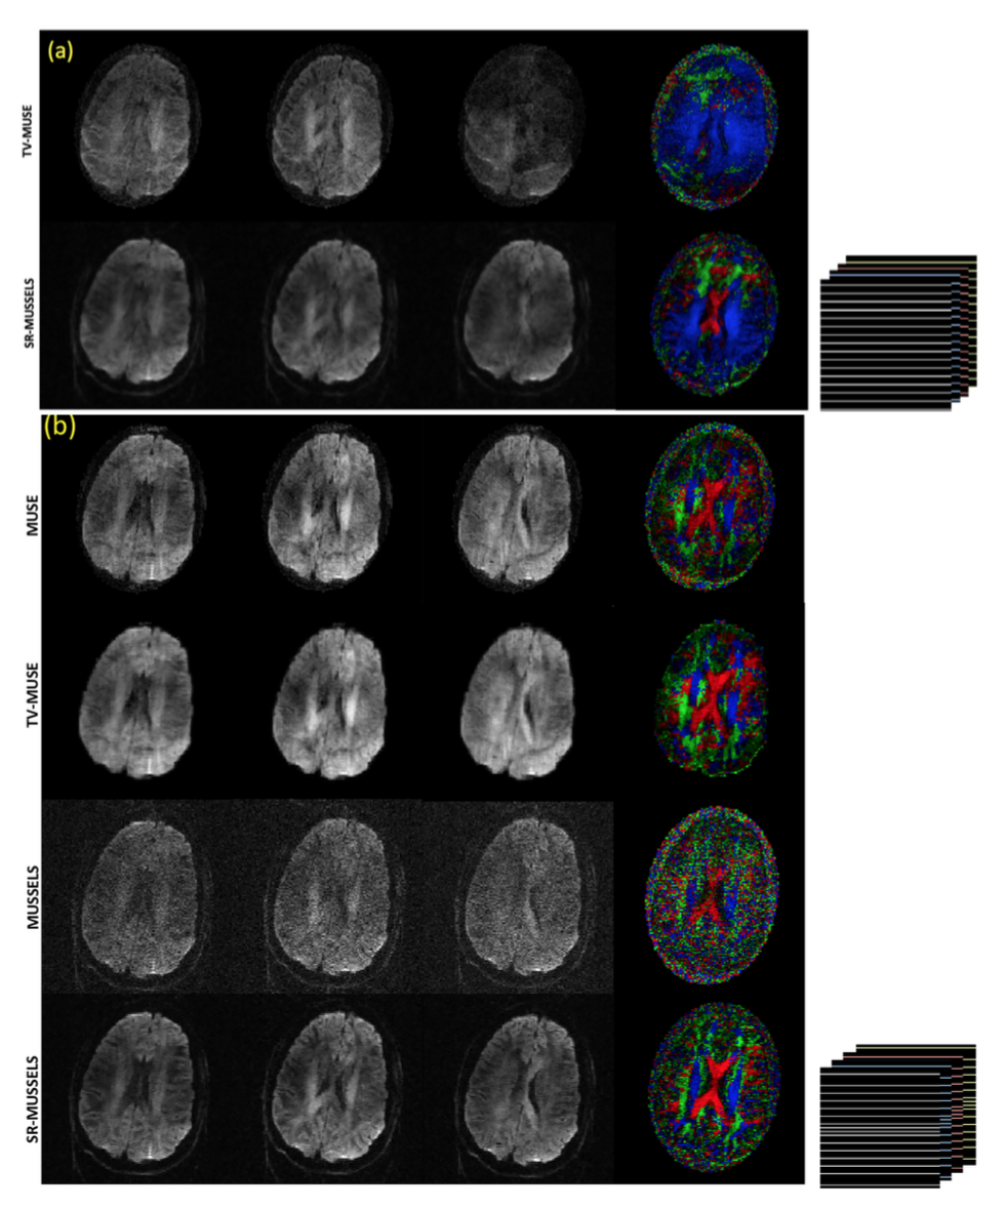

The recovery of 8-shot diffusion data can be challenging due to the fewer number of sampled data points present in each shot. Because of the absence of a fully sampled center k-space, the phase estimates obtained from the shots can be noisy. Hence the reconstructions that depend on the phase estimates may not achieve good unaliasing in such situations. MUSSELS with no additional constraint will generate noisy results since it is hard to characterize the k-space filter corresponding to the phases from the smaller number of samples present in the compact filter. However the reconstruction can be stabilized by adding extra constraints. By using the smoothness regularized reconstruction provided in Eq [14], we show that we can significantly improve the unaliasing for under-sampled acquisitions as well as for data collected with a high number of shots. Figure 7 shows the reconstruction of the 8-shot MS-DWI data using unregularized and regularized methods. To introduce a similar smoothness regularizer into the MUSE framework, a total-variation based regularization was added to the MUSE reconstruction as well. The estimates of phase used in MUSE reconstruction for one of the images (indicated by the colored boxes) are also provided in the figure. The top row shows the reconstruction using MUSE with no TV during the image reconstruction. The left figure used low regularization for phase estimation (the regularization parameter was chosen to give the best reconstruction for the boxed image in 7(a)) while the right figure used higher regularization for phase estimation. The corresponding phase images are given in the panel on right; it shows that the quality of the phase images control the quality of the DWI reconstruction. The second row shows the MUSE reconstruction with TV built into the iterative MUSE implementation. However, as can be appreciated from the images, the TV reconstruction also gets only as better as dictated by the noise in the phase since these reconstructions are inherently phase-based. The third row shows the MUSSELS reconstruction without TV (left) and with TV (right). As expected the images are noisy for the unregularized case. However using the smoothness regularized MUSSELS, we can recover the MS-DWI data reasonably well.

Fig 7: 8 shot fully sampled data. The six DWIs reconstructed using various methods are shown. (a) and (f) shows MUSE reconstruction with no TV during the image reconstruction. They use TV in the estimation of estimate phase. (f) used a higher regularizer than (a) during the estimation of phase. As a result, the DWIs in (f) are denoised while the unaliasing becomes imperfect. (b) and (g) shows MUSE reconstruction with TV regularization added to the image reconstruction step also with (b) using the same phase as (a) and (g) using the same phase as (f). Inclusion of TV to the image reconstruction step has improved the MUSE reconstruction slightly however, the results are dictated by the noise in the phase estimates. (k) and (m) shows the results of MUSSELS without and with SR respectively. It can be appreciated from the color coded FA maps (e) and (l) that MUSSELS without SR achieves the better quality of reconstruction than the TV-MUSE and the results can be further improved by using SR-MUSSELS.

Figure 7: 8 shot fully sampled data. The six DWIs reconstructed using various methods are shown. (a) and (f) shows MUSE reconstruction with no TV during the image reconstruction. They use TV in the estimation of estimate phase. (f) used a higher regularizer than (a) during the estimation of phase. As a result, the DWIs in (f) are denoised while the unaliasing becomes imperfect. (b) and (g) shows MUSE reconstruction with TV regularization added to the image reconstruction step also with (b) using the same phase as (a) and (g) using the same phase as (f). Inclusion of TV to the image reconstruction step has improved the MUSE reconstruction slightly however, the results are dictated by the noise in the phase estimates. (k) and (m) shows the results of MUSSELS without and with SR respectively. It can be appreciated from the color coded FA maps (e) and (l) that MUSSELS without SR achieves the better quality of reconstruction than the TV-MUSE and the results can be further improved by using SR-MUSSELS.